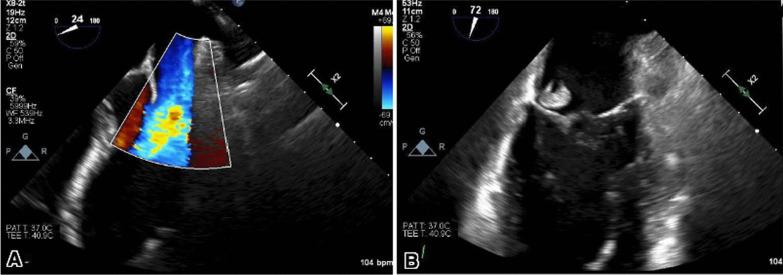

This case report presents a patient with COVID-19 who developed infective endocarditis (IE) and mitral valve perforation caused by methicillin-resistant Staphylococcus aureus on a native mitral valve. Notably, the patient did not exhibit typical IE risk factors, such as intravenous drug use. However, he did possess risk factors for bacteremia, including a history of diabetes mellitus and recent steroid use due to the COVID-19 infection. The diagnosis of IE was crucially facilitated by transesophageal echocardiography.

This case highlights the potential association between COVID-19 and the development of infective endocarditis. Prompt evaluation using transesophageal echocardiography is vital when there is a high suspicion of IE in COVID-19 patients. Further research is required to elucidate the precise relationship between COVID-19 and IE.

本病例报告展示了一名COVID-19患者,该患者发生了感染性心内膜炎(IE),并因耐甲氧西林金黄色葡萄球菌导致原生二尖瓣穿孔。值得注意的是,该患者未表现出典型的IE危险因素,如静脉吸毒。然而,他确实存在菌血症的危险因素,包括糖尿病史以及因COVID-19感染近期使用类固醇。经食管超声心动图对IE的诊断起到了关键作用。

本病例突出了COVID-19与感染性心内膜炎发生之间的潜在关联。当高度怀疑COVID-19患者患有IE时,使用经食管超声心动图进行快速评估至关重要。需要进一步研究以阐明COVID-19与IE之间的确切关系。